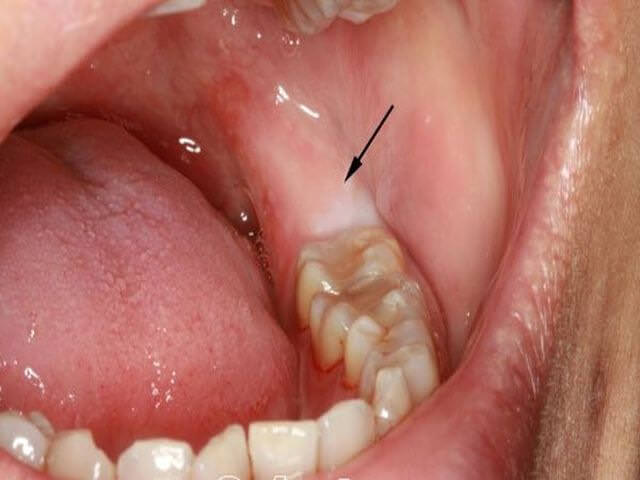

- Направленность зуба мудрости в сторону щеки на первый взгляд не кажется опасной. Однако это мнимое впечатление. Зуб, растущий вбок, регулярно наносит уязвимой слизистой оболочке щеки микроповреждения. Часто приводит к воспалению десны и перекорониту. Усиливает серьёзность ситуации тот факт, что слизистая щёк небогата болевыми рецепторами, поэтому человек порой даже не ощущает причиняемого вреда. В результате щека повреждается изнутри, а область ранения становится воротами проникновения инфекции и сильно воспаляется. Постепенно клетки слизистой под давлением происходящего трансформируются и заменяются чужеродной, более плотной тканью. Это говорит о возникновении новообразований в очаге постоянного травмирования – доброкачественных либо канцерогенных.

Зуб мудрости может стать и причиной перикоронарита. Особенно высок риск этого заболевания при недостаточно или вовсе не прорезавшемся зубе мудрости. Перикоронарит развивается из-за попадания пищевых остатков в десневой «капюшон». Сопровождается это заболевание сильной зубной болью, опуханием десны, неприятным запахом изо рта, некомфортными ощущениями во время приема пищи, разговора, чистки зубов. В отдельных случаях может наблюдаться повышение температуры. Если перикоронарит переходит в глубокую стадию, то велика вероятность развития более опасных заболеваний – периостита (воспаления надкостницы челюсти) и остиомиелита (поражения кости).

Когда зуб мудрости лежит горизонтально, появляются и другие проявления. Это может быть флюс или периостит. Болезнь характеризуется гнойным воспалением надкостницы, когда опухает десна и щека. Это опасно тем, что происходит скопления гноя, который может прорваться в глубоких тканях, что приведет к инфицированию.